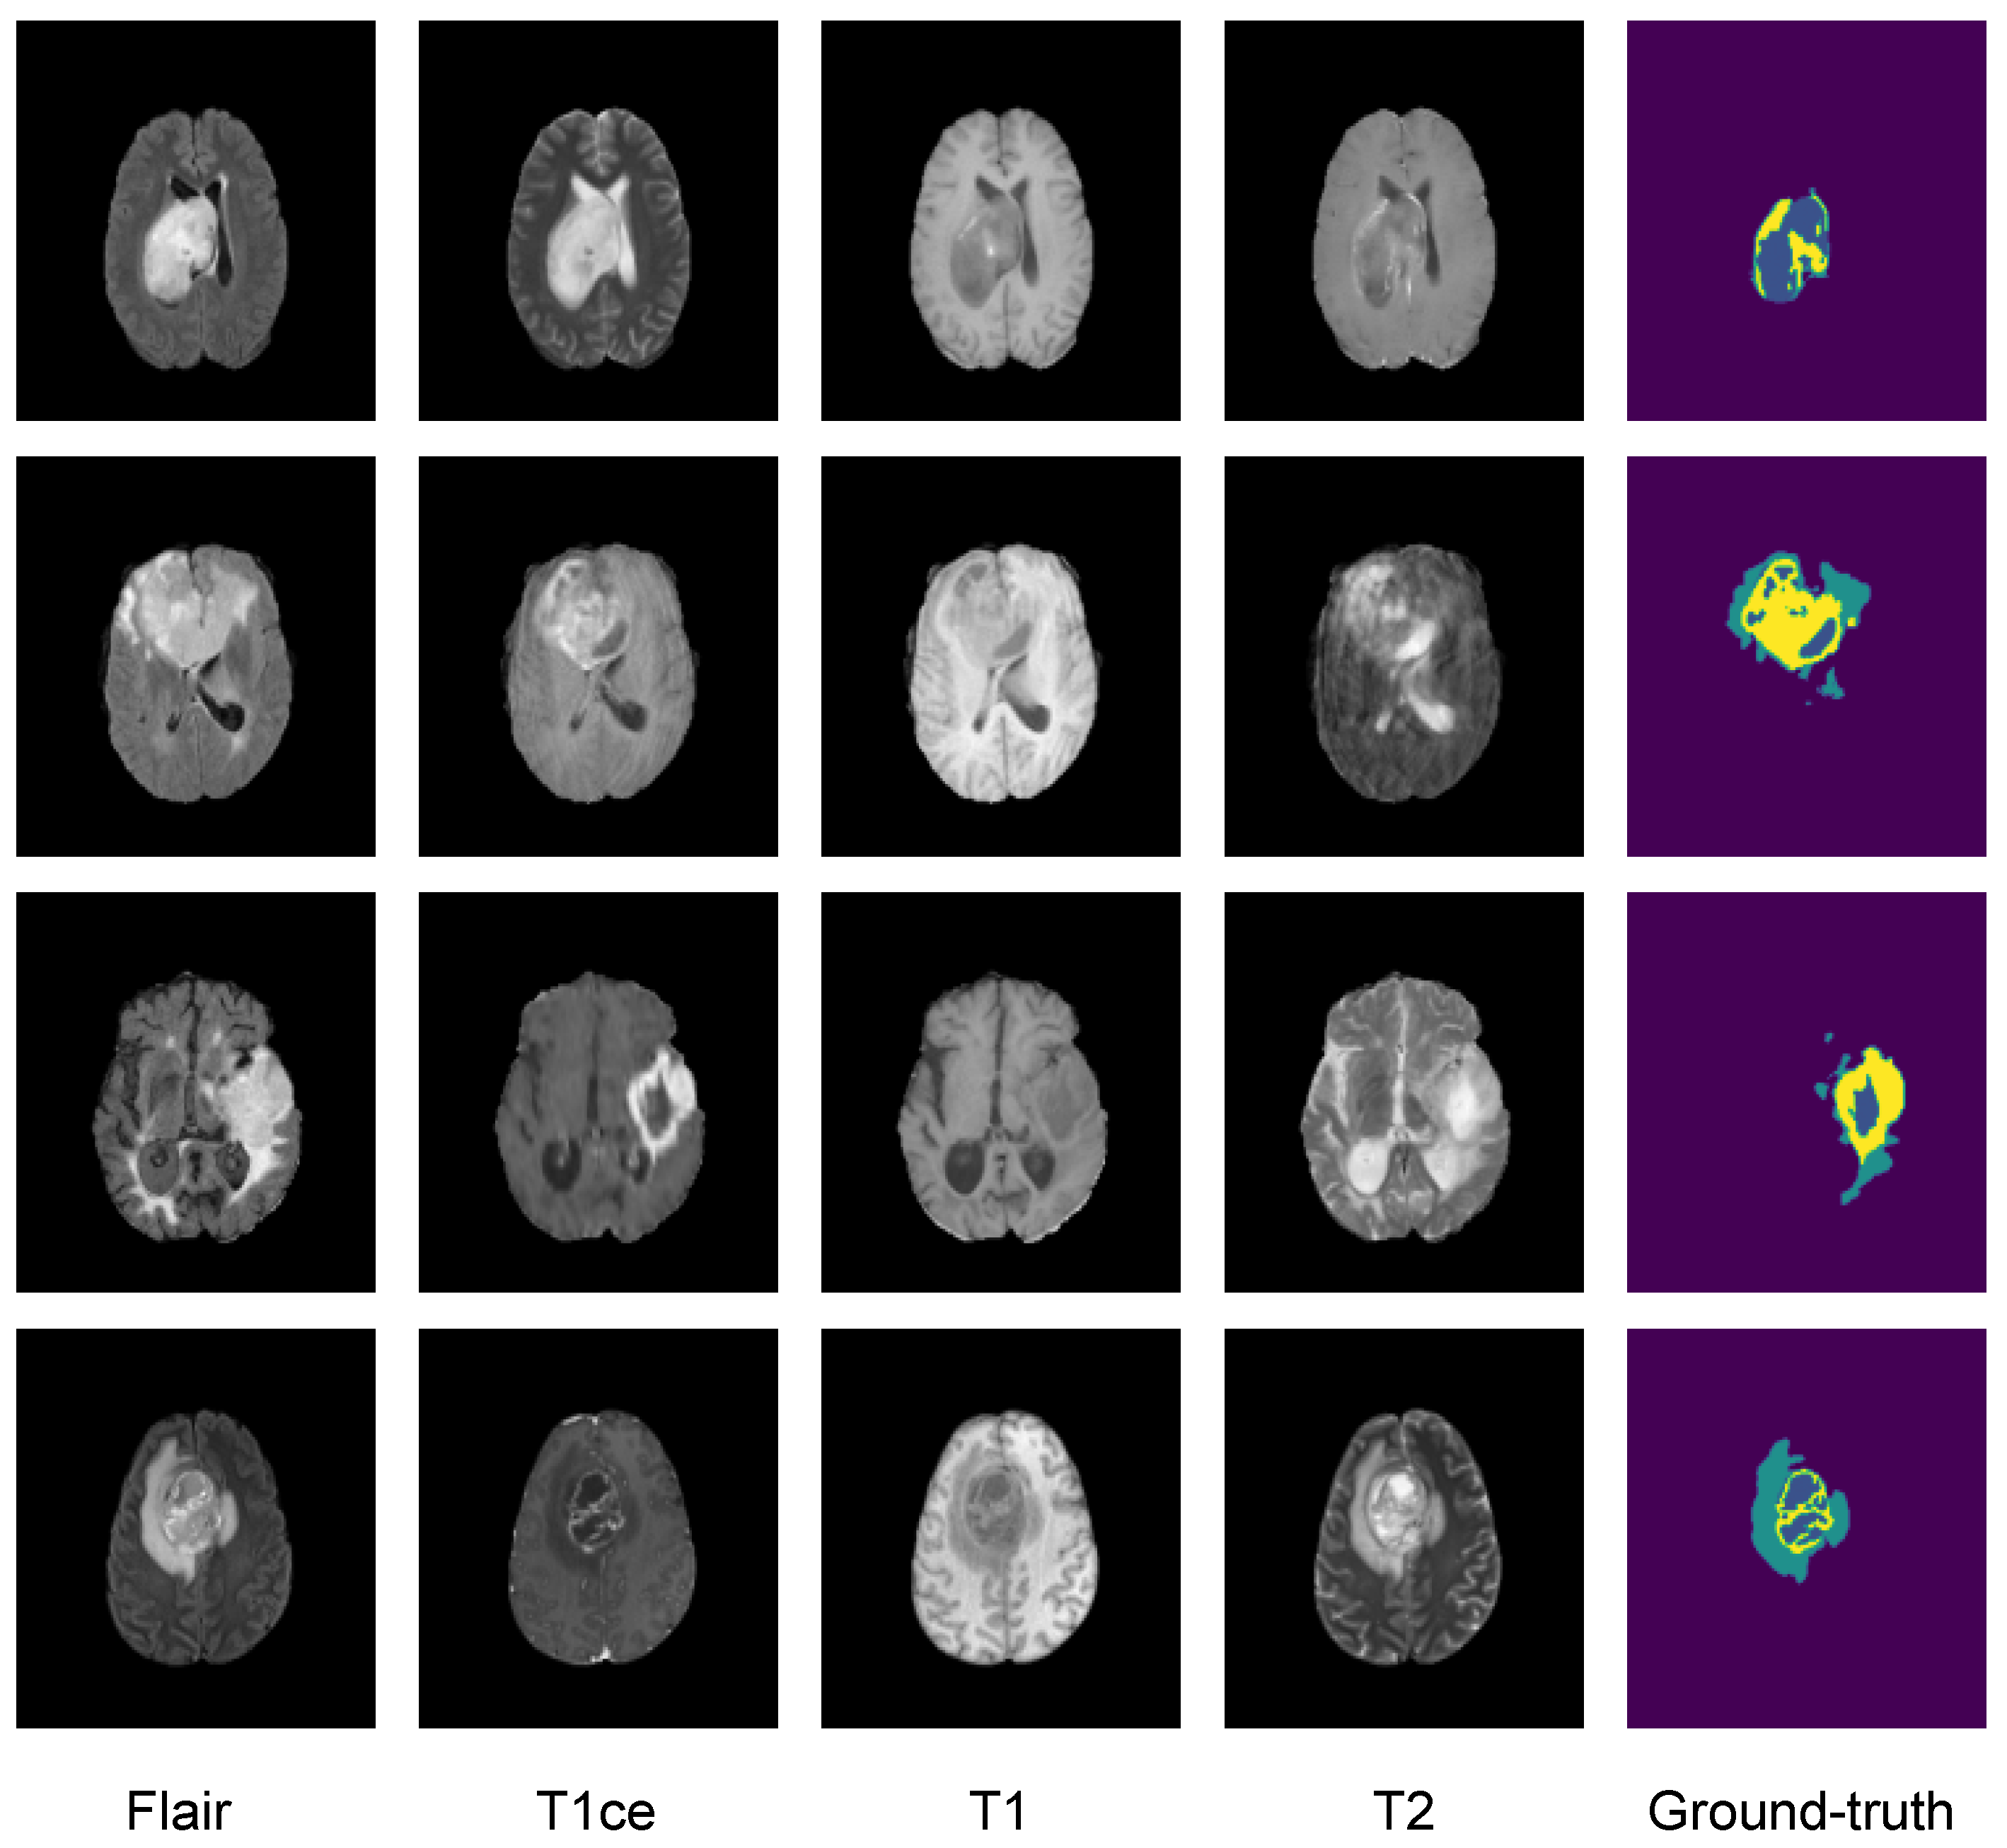

3.2. Dataset

3.3. Image Preprocessing

5.1. First Step Validation

5.1.1. Partial Federated Deep Model

5.1.2. Full Federated Deep Model